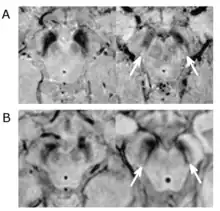

Substantial loss of melanized dopaminergic neurons in the substantia nigra pars compacta (SNpc) is a major characteristic of PD pathogenesis. Many studies have shown that differential prevalence of PD between ethnic groups is due to differences in the number of melanized neurons in the substantia nigra. Most Indians, compared to populations with European origin, have around 40% lower in number of melanized nigral neurons, however, they also tend not to lose these neurons with age. Although Indians do have a lower SNpc volume, this population tends to have a higher neuronal density as well as number of neurons which is hypothesized to be the reason for a lower incidence rate of PD, but this needs to be expanded upon.[5]